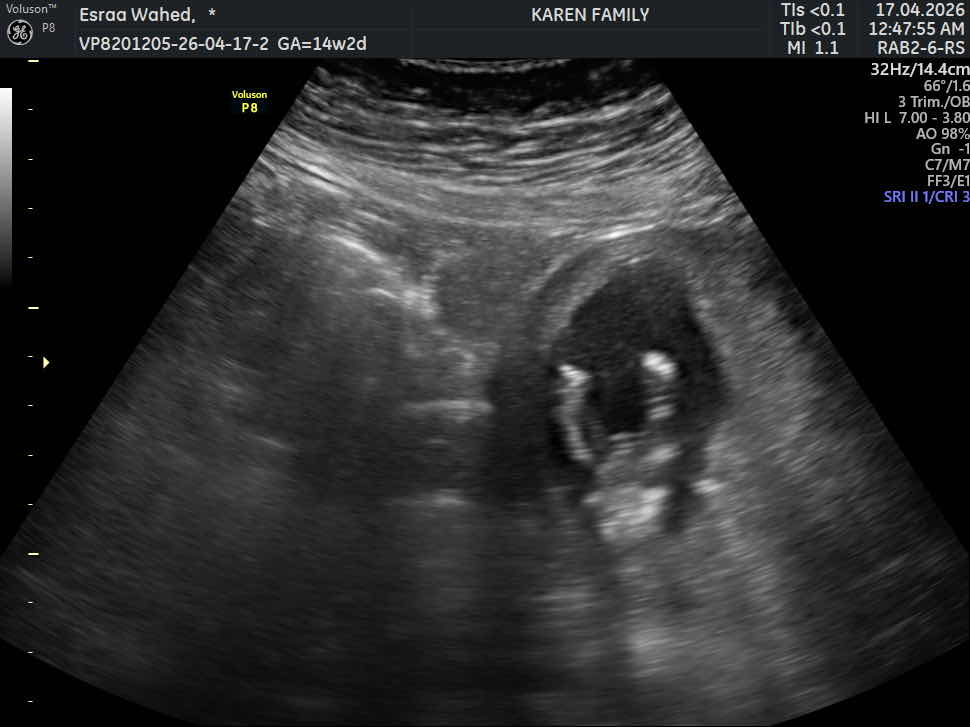

تحديد نوع جنين اول يوم في الشهر الرابع

هل يمكن تحديد نوع جنين اول يوم في الشهر الرابع في هذا السونار

غالبا ذكر والله أعلم..تابعي الفحص 0 2026-04-22T09:59:42+00:00 2026-04-22T09:59:42+00:00

غالبا ذكر والله أعلم..تابعي الفحص